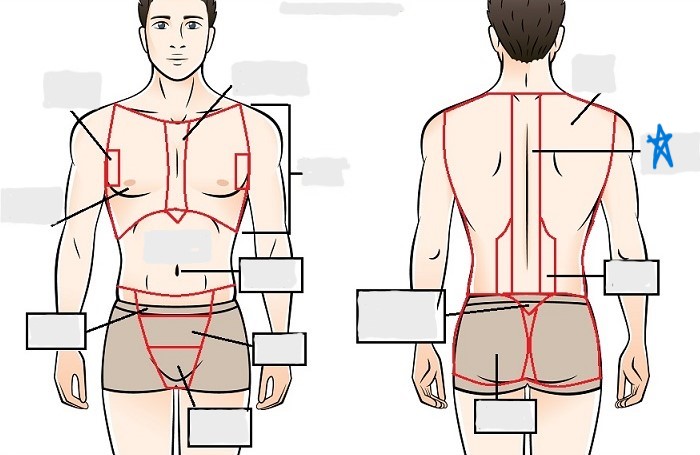

axial

cephalic

occipital

frontal

otic

orbital

nasal

oral

mental

cervical

dorsal

scapular

vertebral

lumbar

sacral

gluteal

thoracic

sternal

mammary

axillary

abdominal

umbilical

pelvic

inguinal

pubic

perineal

appendicular

acromial

brachial

antecubital

olecranal

antebrachial

carpal

manus

coxal

femoral

patellar

popliteal

crural

sural

peroneal

calcaneal

plantar